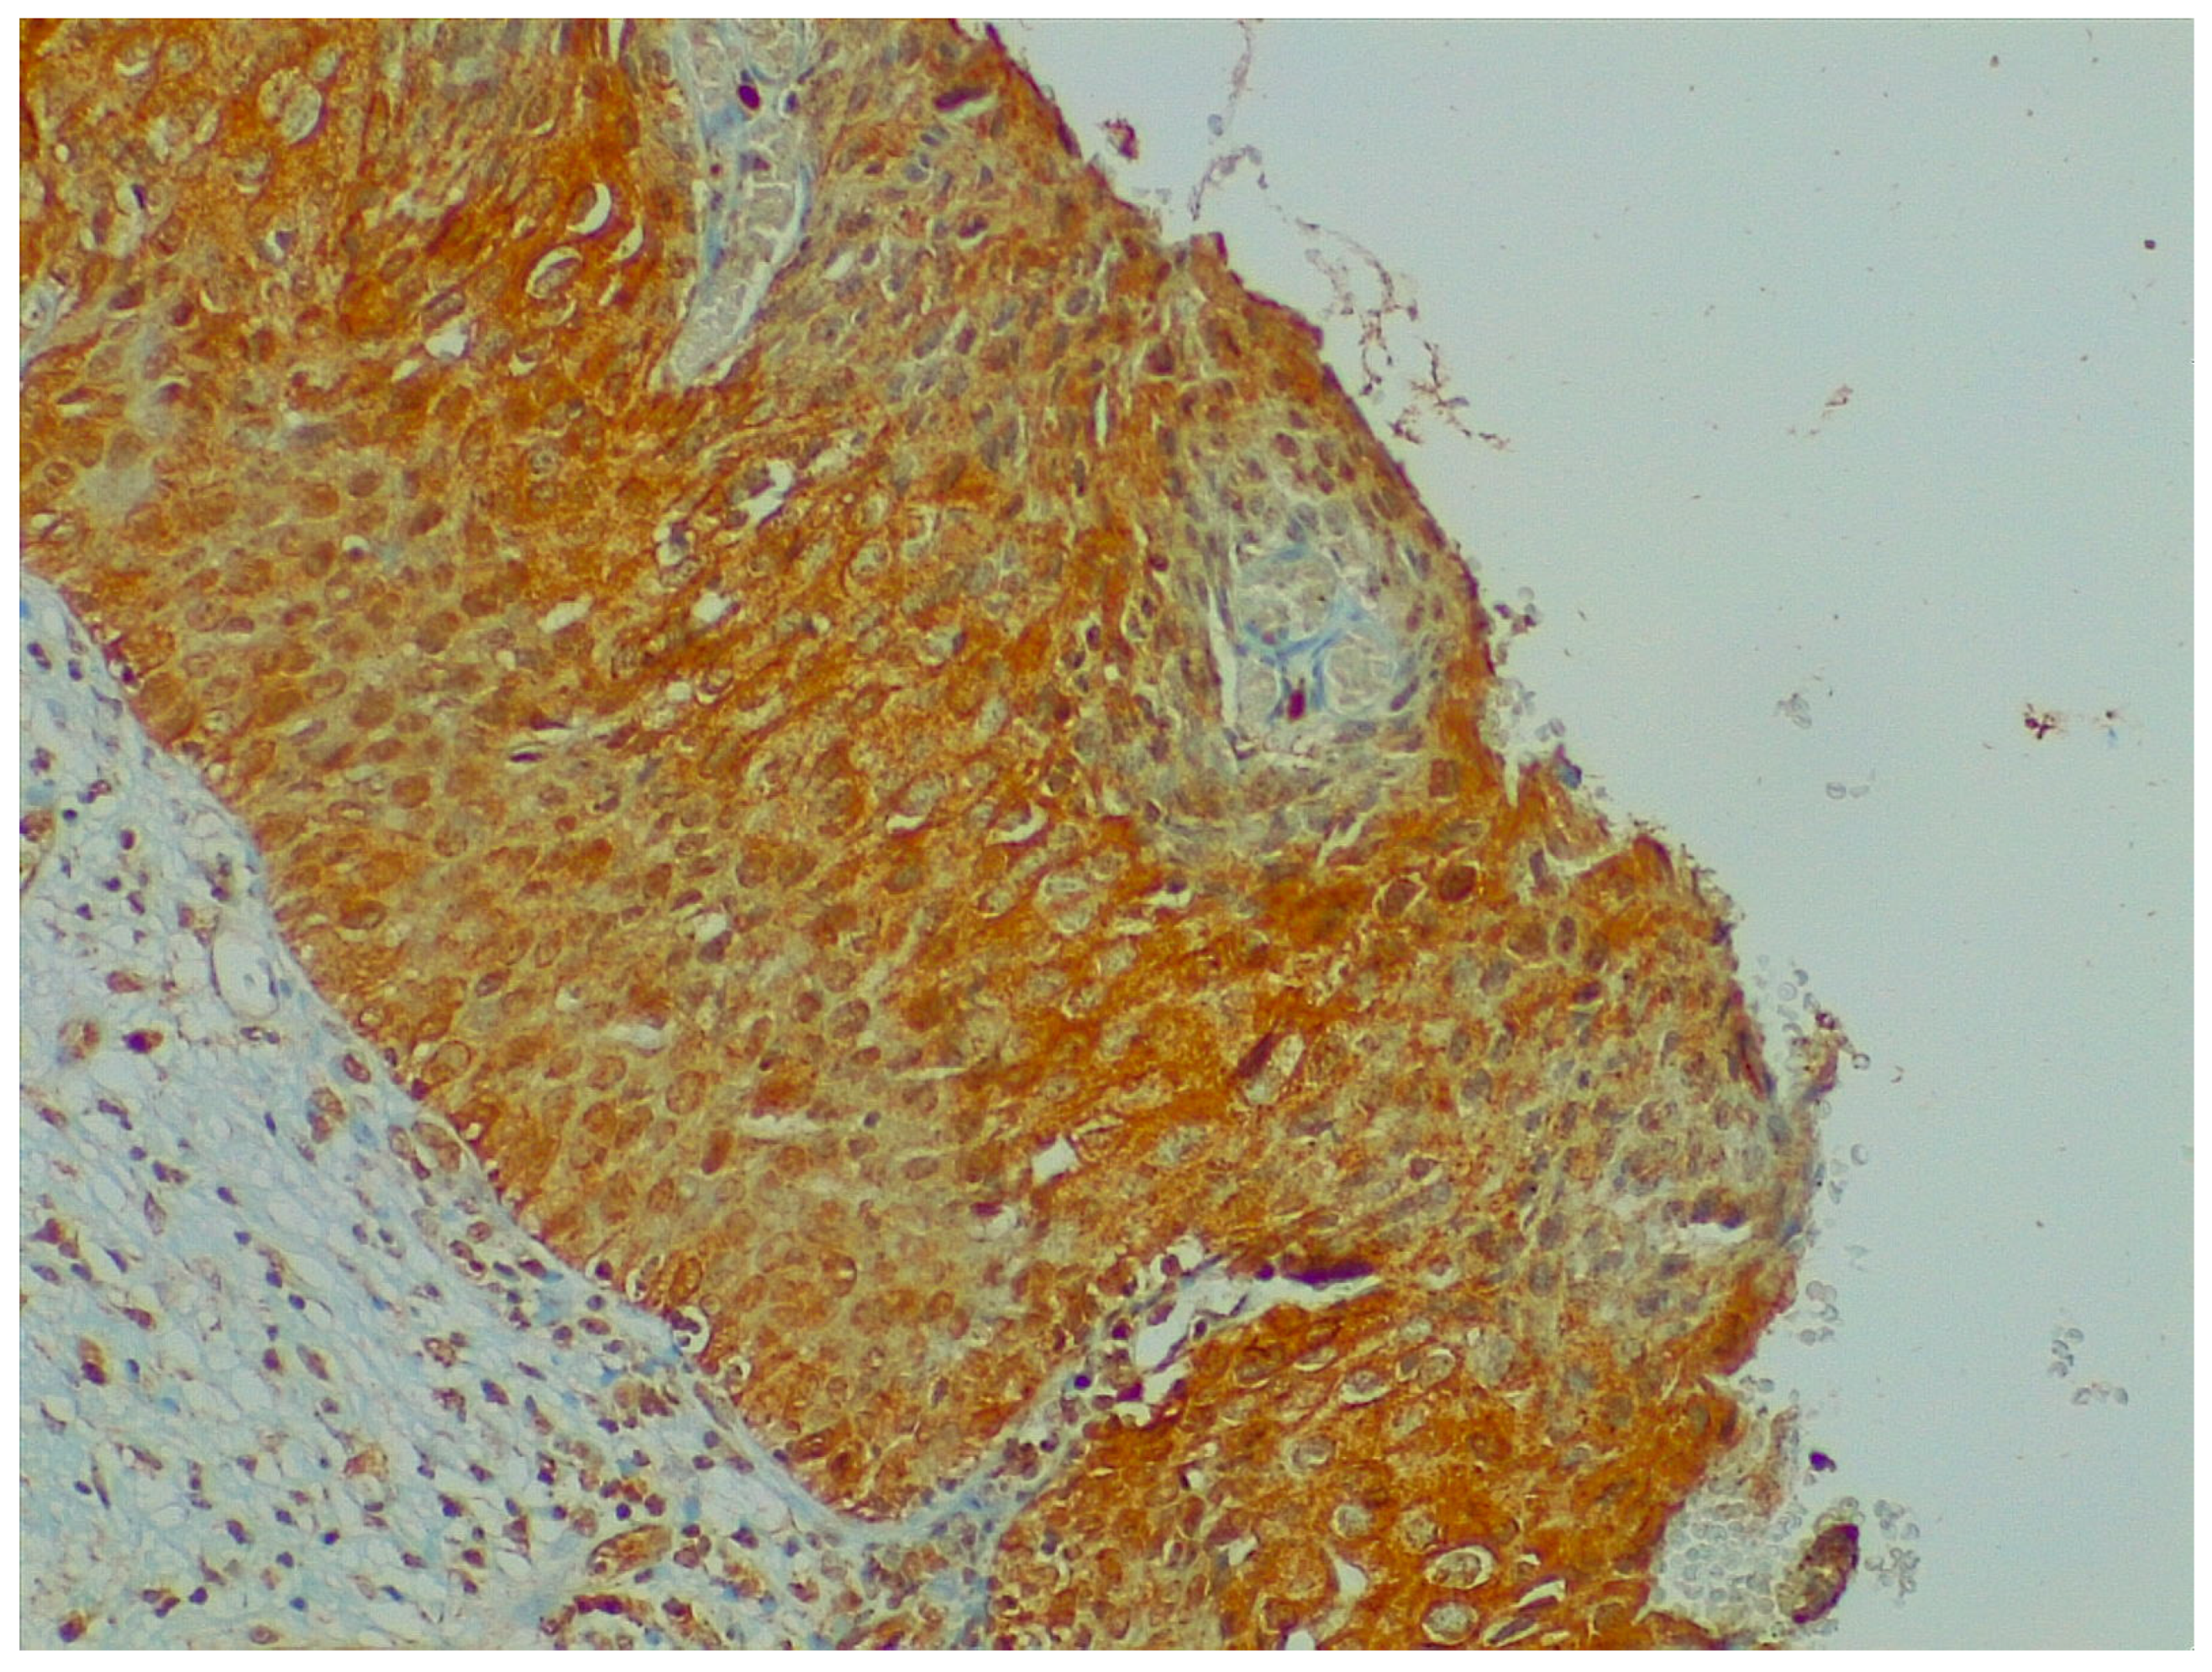

4.1. Neurotrophin Expression in Cervical Dysplastic and Neoplastic Lesions